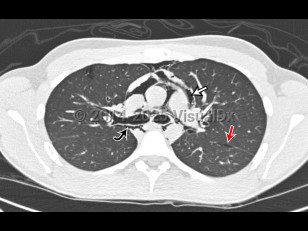

Pneumomediastinum is the presence of air in the mediastinum. It is caused by injury, most often esophageal or intestinal perforation. It is also seen as a result of aggressive bag-valve mask ventilation during resuscitation and intubation as well as a result of barotrauma in intubated patients.